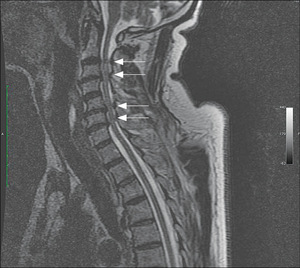

Zakres objawów klinicznych występujących po urazach kręgosłupa jest bardzo szeroki. W zależności od siły urazu, powstałych uszkodzeń oraz miejsca (poziomu) uszkodzenia chory może zgłaszać odmienne dolegliwości. Ich skala jest również wprost proporcjonalna do zakresu i stopnia uszkodzenia bądź ucisku struktur nerwowych. Czas trwania impresji na rdzeń kręgowy lub korzenie nerwów wpływa niekorzystnie na ich funkcjonowanie – przedłużający się ucisk drastycznie pogarsza możliwość powrotu ich prawidłowej, fizjologicznej czynności. Obrażenia odcinka szyjnego manifestują przeważnie się ubytkami neurologicznymi w obrębie obręczy barkowych i kończyn górnych. Masywne uszkodzenie rdzenia na tym obszarze może spowodować wystąpienie tetraplegii [11], niewydolności oddechowej oraz objawów z niższych poziomów rdzenia kręgowego (rycina).